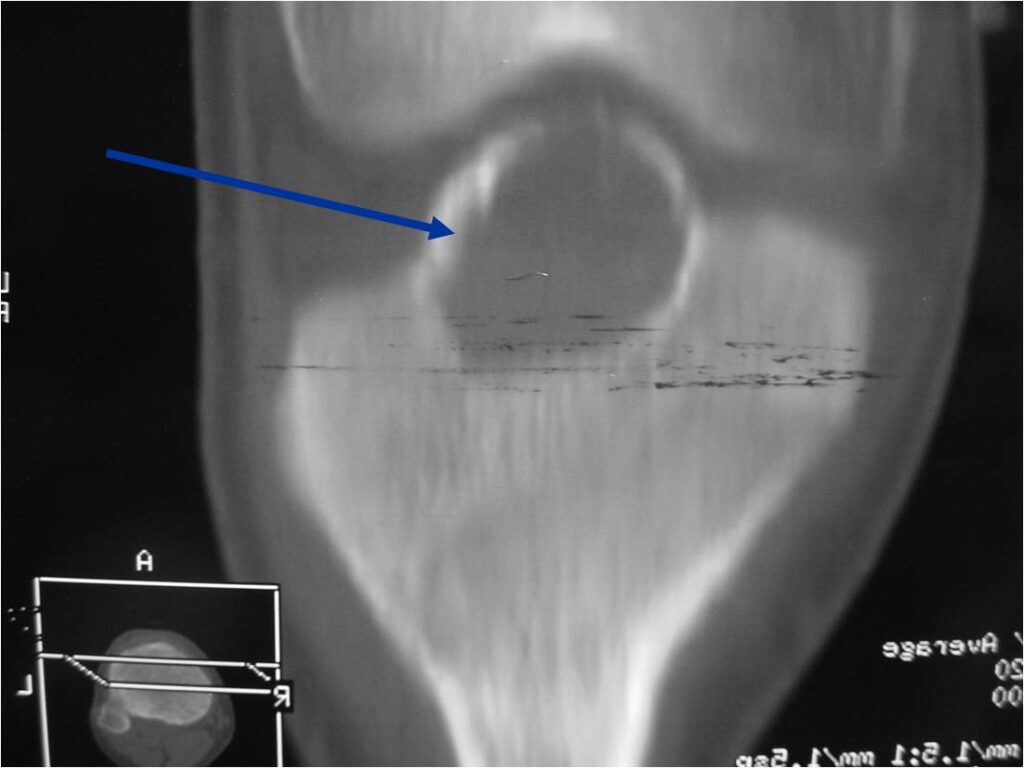

- Presents as a highly defined/well circumscribed geographic oval/round lytic defect

- Surrounded by rim of sclerotic bone

- Usually in epiphyseal region

- Lesion ranges from 3 cm to 6 cm diameter

- Usually radiolucent

- May have fine trabeculae and irregular calcifications

- Calcifications are often better detected with a CT scan but are not uniformly present

- Lesions may expand the bone and new periosteal bone may form

- Bony end plate, cortex, bone contour are unaffected

- (Plain x-ray appearance)

- Geographic lytic lesion IA/IB margin of sclerosis

- Usually Eccentric more often than Central in the bone

- Rarely expansile (rarely penetrates the cortex)

- Calcified chondroid matrix 30%-50% of cases

- Often better detected with a CT Scan

- Periosteal Reaction 30-50% of cases

- Usually occurs in Adjacent Diaphysis/Metaphysis since epiphysis is intraarticular and not surrounded by periosteum